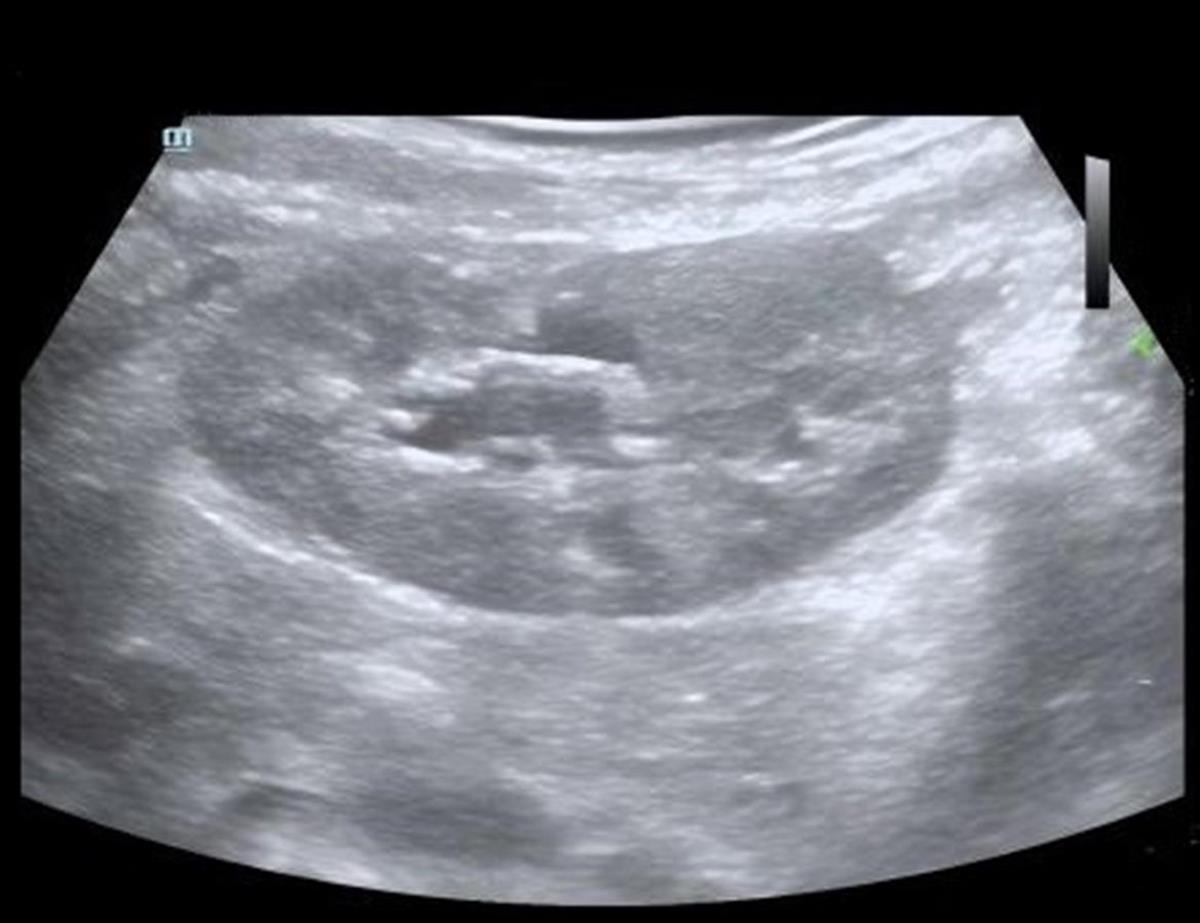

“去年一整年,这个囊肿都挺‘安分’的,可半个月前复查时,囊肿却长到了乒乓球大小。”浩浩妈妈回忆,当时的超声及CT检查结果提示,孩子的囊肿达到BosniakII级,大小约45×40毫米,因为担心囊肿继续增大影响健康,一家人赶紧来到武汉儿童医院泌尿外科就诊。

术后超声影像图